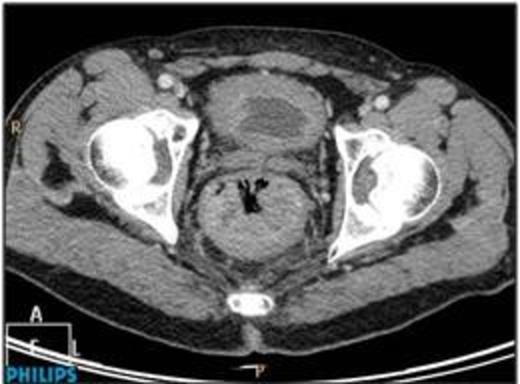

A 61 year old male was admitted having collapsed at home. He was pale, in sinus tachycardia, and normotensive with a palpable lesion per rectum. There was no hepatomegaly or regional lymphadenopathy. A colonoscopy, performed fourteen months earlier, showed tubular adenoma with low grade dysplasia in the transverse colon. Contrast CT abdomen and pelvis on admission revealed a large mass in the posterior rectum extending to the lateral wall (Figure 1).